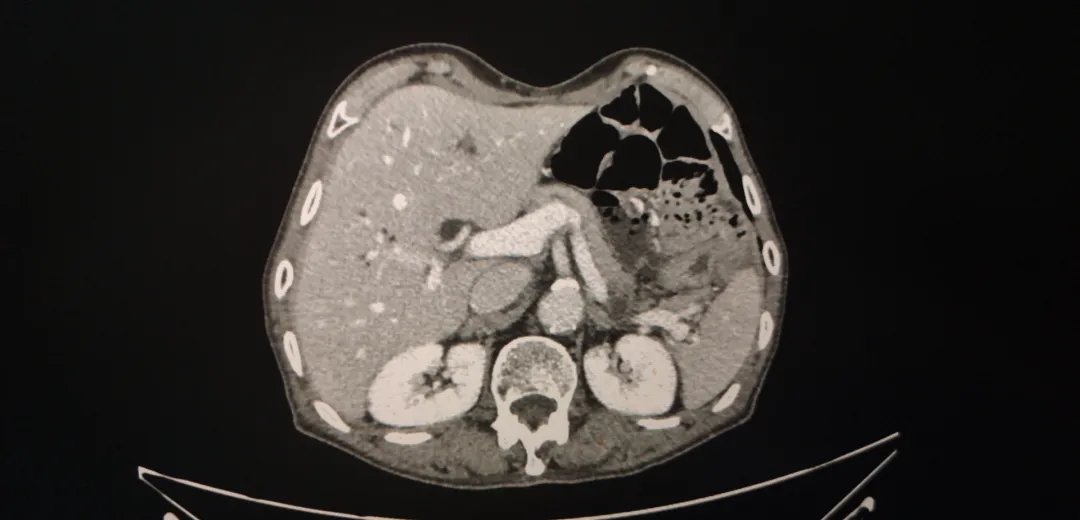

图1-1  2018-4-4  箭头为胃周肿大淋巴结

图1-2 2018-4-4 箭头为胃部肿瘤,胃壁增厚明显